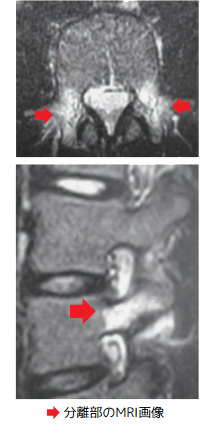

腰椎分離症(成長期の腰痛)

スポーツによる繰り返しの負担で、成長期の腰椎(背骨)の一部が疲労骨折を起こし、骨が分離する状態です。

10〜18歳ごろの運動をするお子さんに多く、特に野球・体操・サッカーなど腰を反らす・ひねる動作が多い競技に関連しています。

診断にはX線・MRI・CTを用いて、疲労骨折の有無や進行度を評価します。

Q3. どんな検査で分かりますか?

A. X線やMRI、必要に応じてCTで分離の有無や骨の状態を詳しく調べます。骨の癒合が期待できる時期に適切な対応をすることが大切です。